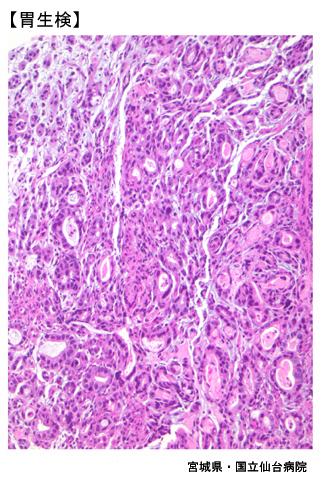

Múltiples Metástasis de Cáncer del Intestino Delgado y Grueso que mostraron forma similar a IIa+IIc (Caso presentado por Dr. Yokota del Hospital Nacional de Sendai, prefectura de Miyagui)

Tumor Epitelial Maligno/Adenocarcinoma

estómago(región)/mas de dos

Micro